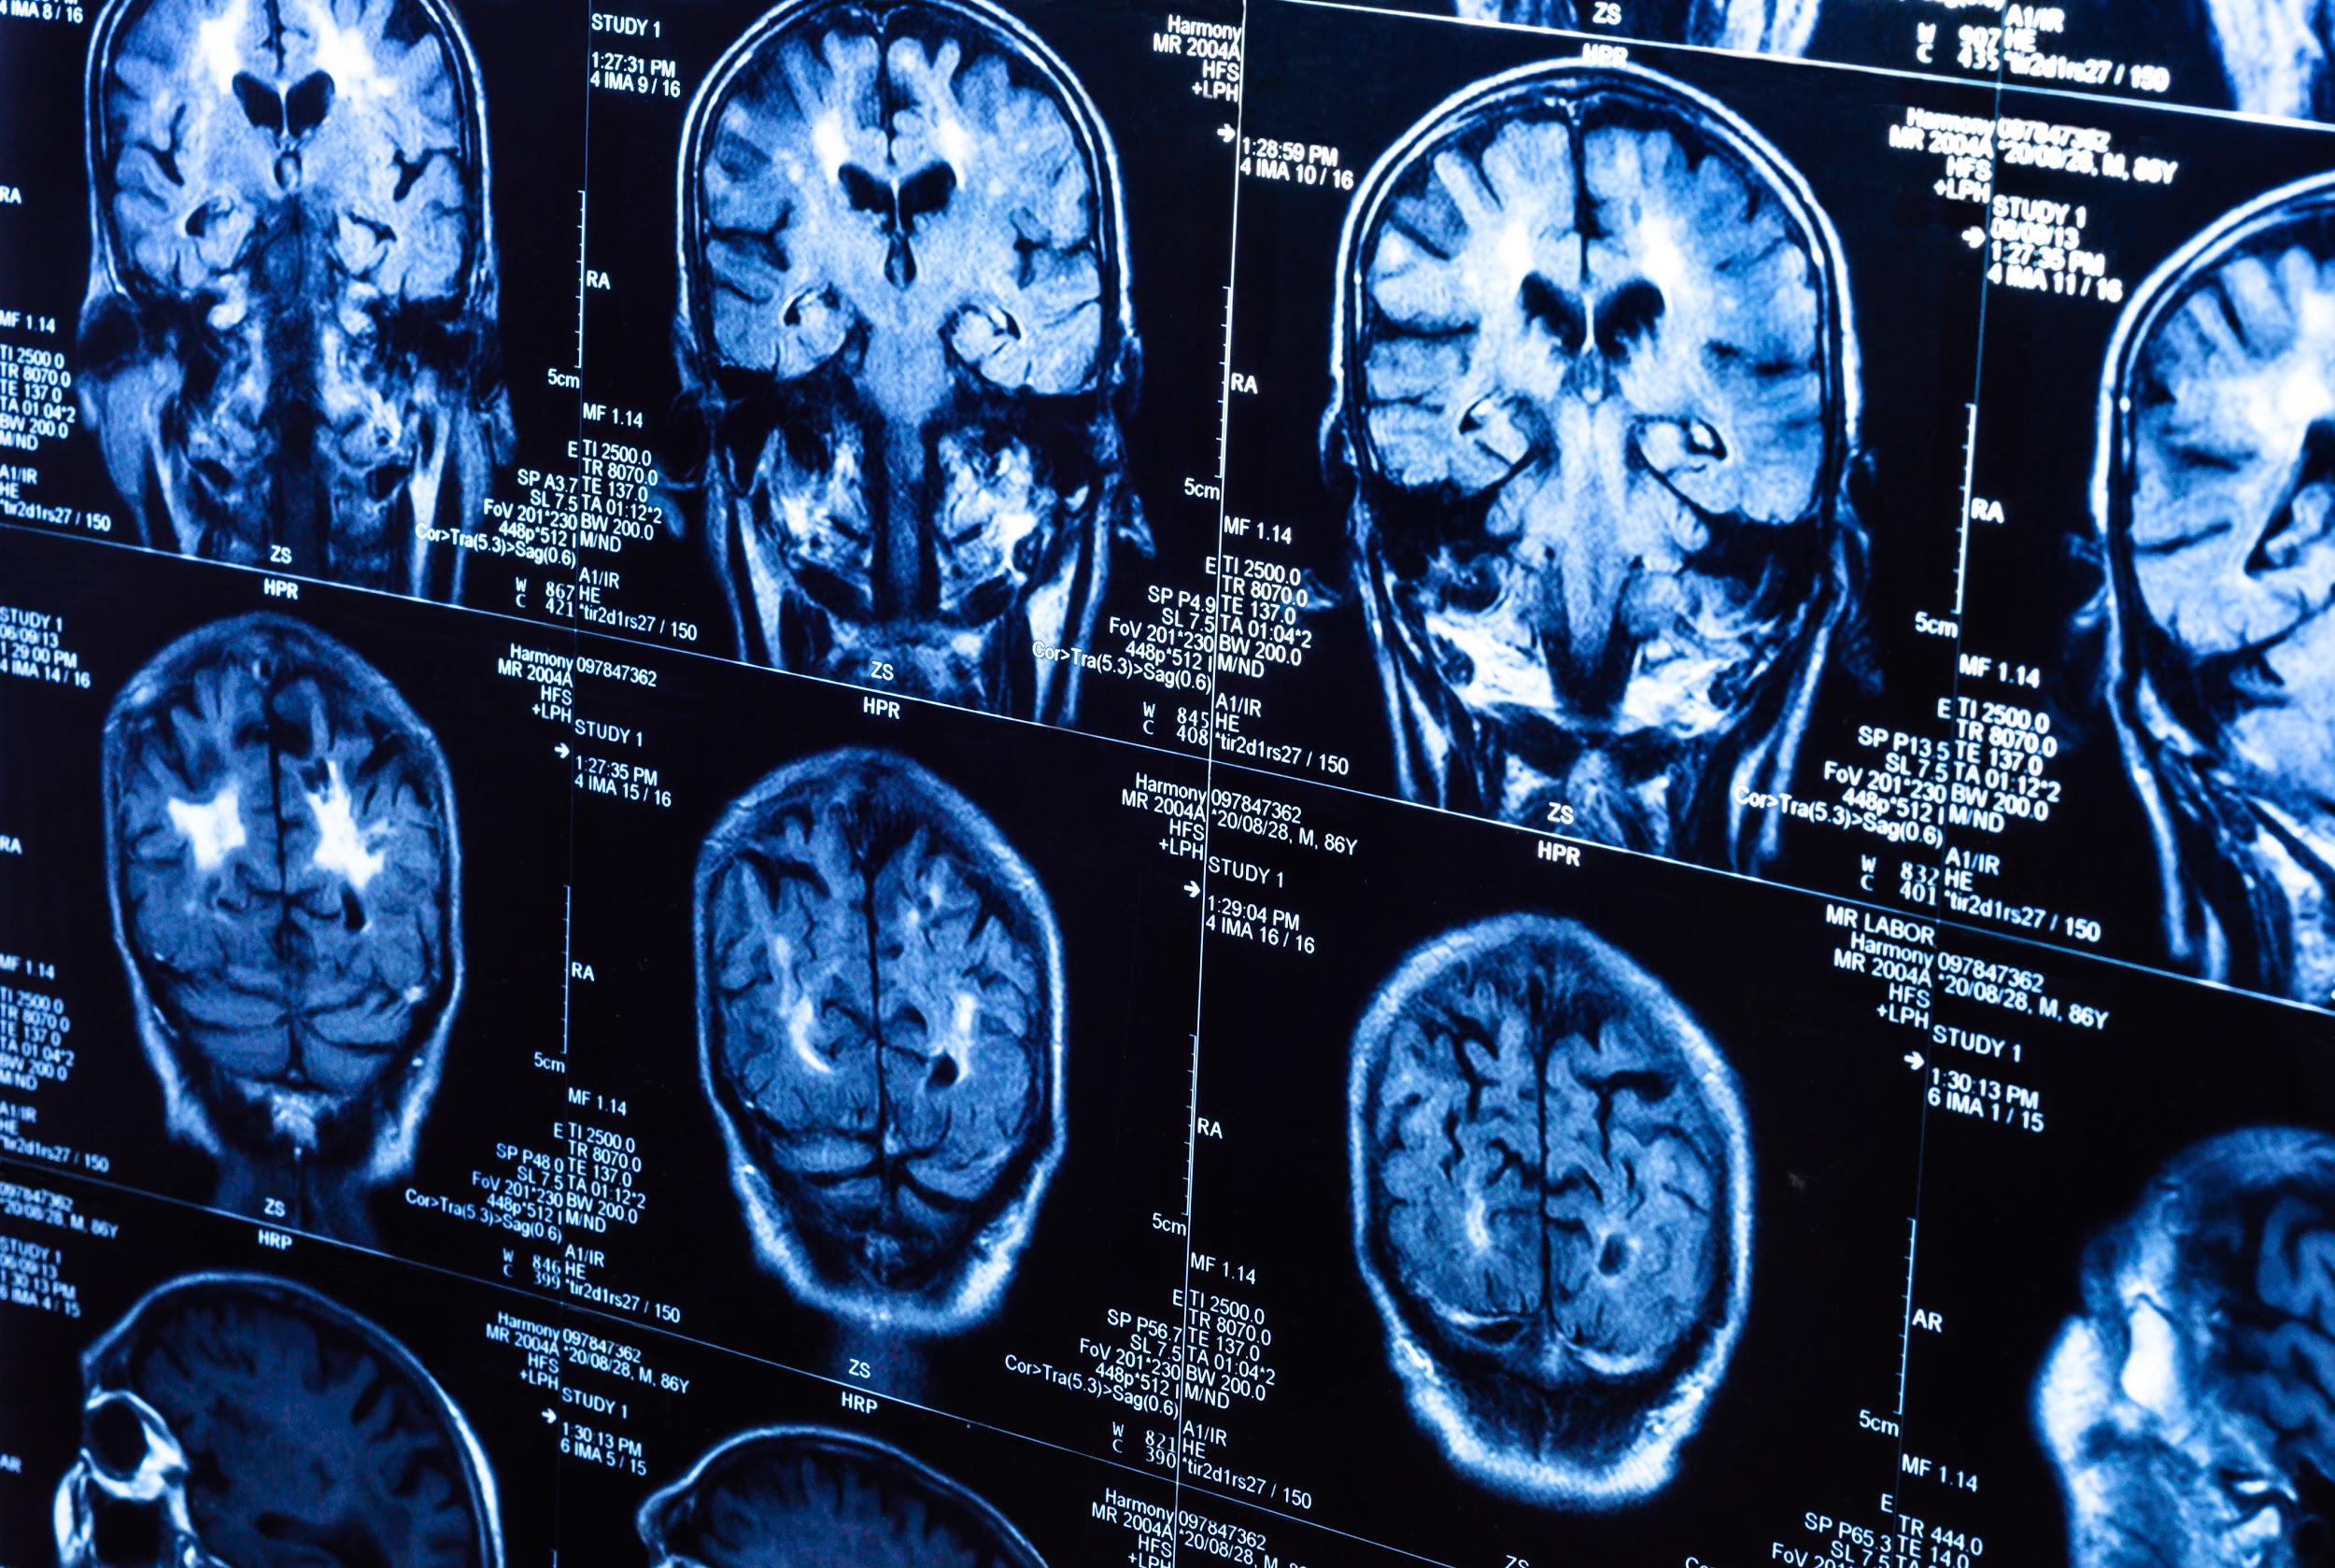

A California medical imaging group practice says vulnerabilities in its picture archiving and communications system left patient data at risk of unauthorized access for more than a year.

The practice’s administrator tells Information Security Media Group that the vulnerabilities left accessible “names of about 100,000 patients on a worklist.” The German security firm Greenbone Networks discovered the flaws while it was conducting its own research, the administrator says.

The vulnerabilities in the PACS included open ports and authentication issues, the administrator says. The practice did not reveal the brand of the PACS system.

An article was published in ProPublica in September 2019 based on findings from a German research company, Greenbone. At that time it was reported that there were images exposed for around 5 million patients in the US alone, plus millions more from around the world.

By the time it was all said and done, they found that there were over 5 million patients with images exposed in some states all by themselves. And they published a really cool map of the US showing how many patients had images exposed by state. GA and FL had over 1 million patients with images exposed and California, where Sutter Buttes in Yuba City is located, had over 10 million patients with exposed images.

There are millions of images from thousands of providers still exposed on the internet. Apparently no one is paying attention at the healthcare facilities. But you know who is paying attention? The criminals are. They see these announcements and take it as their queue to try to exploit this vulnerability to do even more damage.